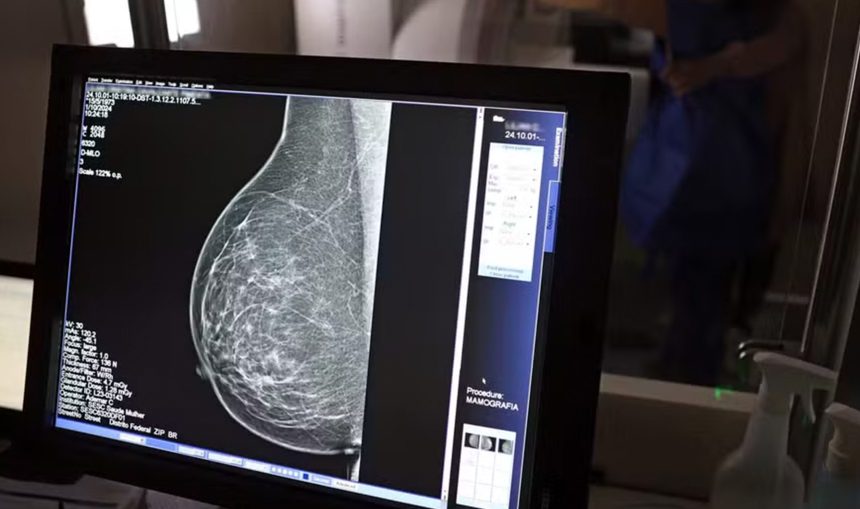

A pesquisa foi conduzida pela Sociedade Europeia de Cardiologia e publicada na revista científica European Heart Journal. O estudo mostra que sistemas de inteligência artificial conseguem identificar e avaliar depósitos de cálcio nas artérias da mama por meio de imagens de raio-x.

Essa calcificação arterial costuma aparecer em mamografias de rotina e não está relacionada a tumores. No entanto, diversos estudos apontam que a presença desses depósitos pode estar associada a fatores de risco cardiovascular e ao desenvolvimento futuro de doenças cardíacas.

Com o auxílio da inteligência artificial, os pesquisadores classificaram a quantidade de cálcio presente nas artérias mamárias em quatro níveis: grande, moderada, leve ou ausente.